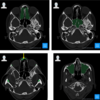

what does this CT scan show?

CT scan of the head in the coronal plane showing left maxillary sinusitis

what sinuses do you see in the CT scans?